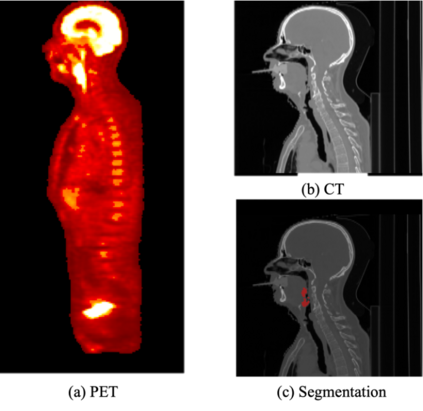

The 5-year survival rate of Head and Neck Cancer (HNC) has not improved over the past decade and one common cause of treatment failure is recurrence. In this paper, we built Cox proportional hazard (CoxPH) models that predict the recurrence free survival (RFS) of oropharyngeal HNC patients. Our models utilise both clinical information and multimodal radiomics features extracted from tumour regions in Computed Tomography (CT) and Positron Emission Tomography (PET). Furthermore, we were one of the first studies to explore the impact of segmentation accuracy on the predictive power of the extracted radiomics features, through under- and over-segmentation study. Our models were trained using the HEad and neCK TumOR (HECKTOR) challenge data, and the best performing model achieved a concordance index (C-index) of 0.74 for the model utilising clinical information and multimodal CT and PET radiomics features, which compares favourably with the model that only used clinical information (C-index of 0.67). Our under- and over-segmentation study confirms that segmentation accuracy affects radiomics extraction, however, it affects PET and CT differently.